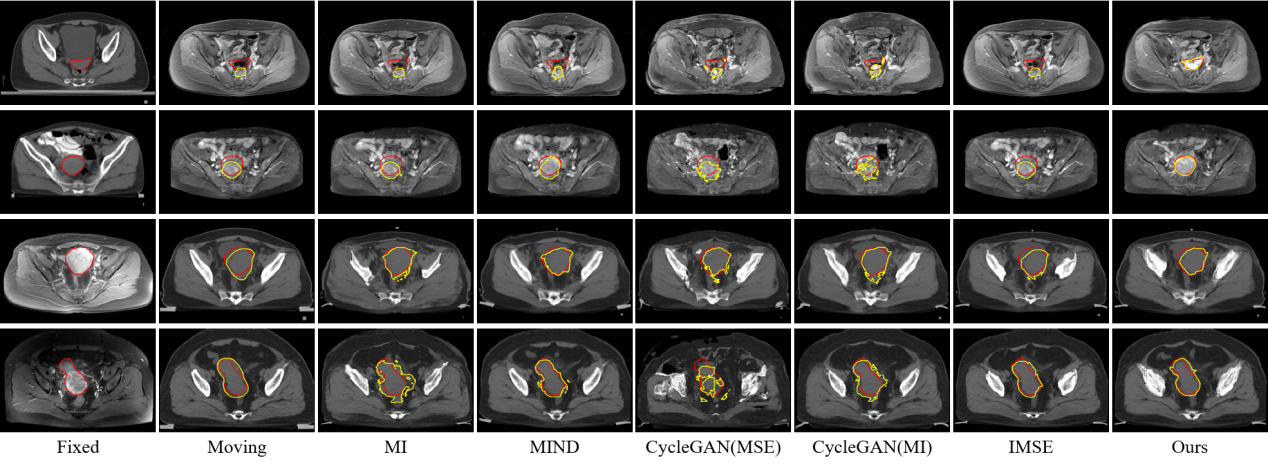

研究結(jié)果表明,SynMSE 在L2R 2022 CT-MR腹部數(shù)據(jù)集、臨床宮頸CT-MR數(shù)據(jù)集以及CuRIOUS MR-US腦數(shù)據(jù)集上均取得了最優(yōu)配準性能。與傳統(tǒng)方法相比,SynMSE顯著提升了Dice系數(shù)、降低了HD95與TRE誤差,實現(xiàn)了在復雜模態(tài)差異下的高精度解剖結(jié)構對齊。圖4-圖6分別為所提出方法在三個數(shù)據(jù)集上的定性結(jié)果展示,紅色標注代表固定圖像的目標器官區(qū)域,黃色標注代表浮動圖像與配準后圖像的目標器官區(qū)域。表示圖中結(jié)果顯示,SynMSE更好的克服了多模態(tài)圖像間的復雜分布差異,不僅實現(xiàn)了更精確的配準效果,而且有效保持了組織邊界與解剖拓撲的完整性,明顯優(yōu)于現(xiàn)有方法。

圖5:所提出方法與現(xiàn)有方法在臨床宮頸CT-MR數(shù)據(jù)集上的定性效果